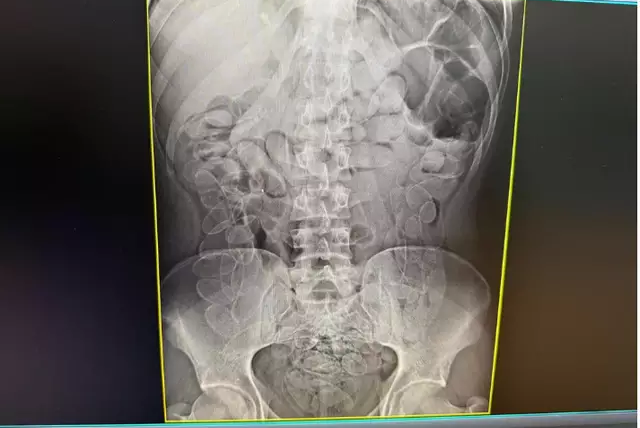

Após entrevistas, os indivíduos confessaram ter ingerido o entorpecente. Eles foram encaminhados sob custódia ao hospital local, onde exames de imagem confirmaram a presença das cápsulas no trato digestivo. Após expelirem cerca de 4 kg da droga, os suspeitos receberam alta e foram conduzidos à Delegacia de Polícia Federal, onde foram autuados em flagrante por tráfico internacional de drogas.